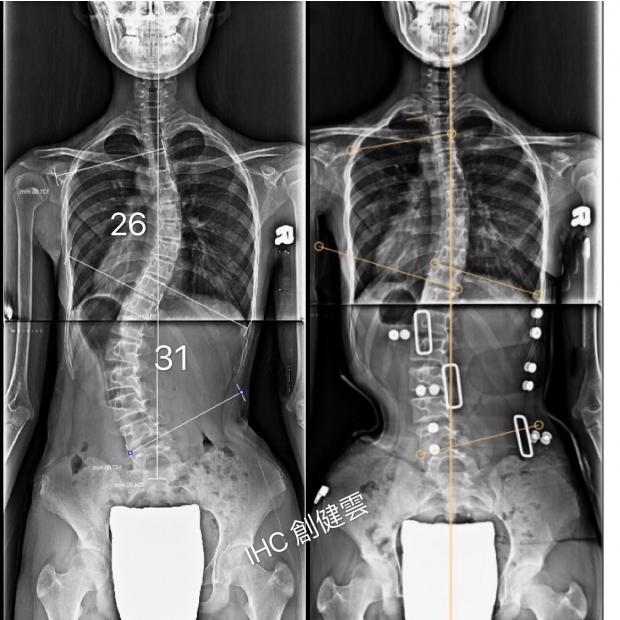

14歲S型脊椎側彎女孩

胸彎26度,腰彎31度